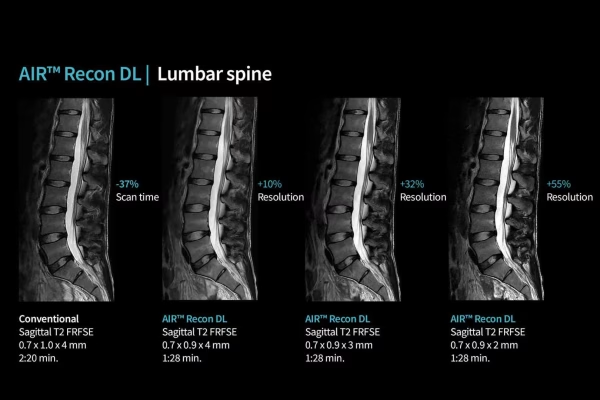

IRM GE Signa Explorer 1.5T